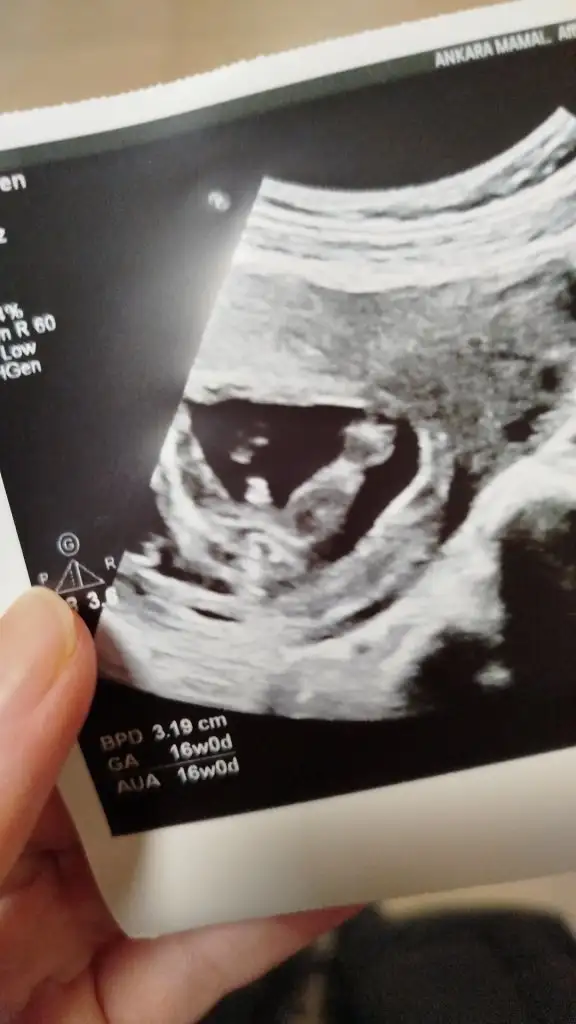

Evet 12. Haftada da erkek dediler sonra emin olmak için başka doktora gittim o da erkek dedi 16. Hafta daÖncesinde de tahminde bulundular mıydı erkek ya da kız diye

Banada 12nde %90 kız dendi 14 de başka doktor erkek dedi 16 ya kaldımEvet 12. Haftada da erkek dediler sonra emin olmak için başka doktora gittim o da erkek dedi 16. Hafta da

Seninki muhtemelen kız az çok anlıyorum gibi artıkBanada 12nde %90 kız dendi 14 de başka doktor erkek dedi 16 ya kaldım

Teşekkür ederim kız ağırlıklı oldu belli olsun haber vereceğimSeninki muhtemelen kız az çok anlıyorum gibi artık